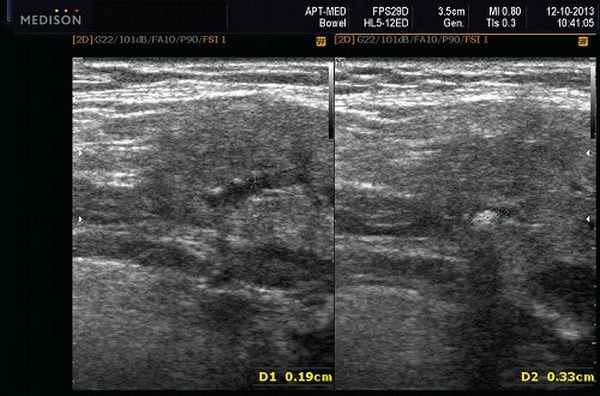

1. Первую методику использовали при наличии конкрементов небольшого размера (1—2 мм), не фиксированных, а подвижных вдоль протока (рис. 1). При этом способе проводился захват камня специальной «корзиной» или внутрипротоковыми щипцами и процедура его извлечения осуществлялась через заранее разбужированное устье без хирургического доступа.

Рис. 1. Удаление конкремента. а — протоковыми щипцами; б — «корзиной».

Данная методика по сути явилась наиболее щадящей и миниинвазивной, но, к сожалению, такие идеальные условия для ее применения в наших наблюдениях встретились лишь у 92 из 317 пациентов. При этом в 14 случаях конкременты располагались в околоушной слюнной железе, а в 78 — в подчелюстной.